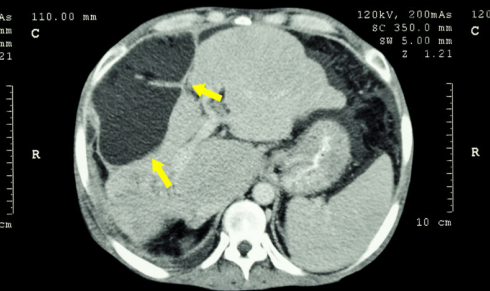

假期回到家后 , 妈妈发现小张一直在呕吐 , 肚子也一天天变大 , 这可把父母吓坏了 , 害怕自己的女儿未婚先孕 , 就赶紧带着女儿到医院检查 , 经过多项检查后 , 发现小张并没有怀孕 , 但却查出了肝癌 , 且肿瘤已经从肝内转移 , 遍布整个腹腔 。

这个消息让一家人愣住了 , 母亲坐在地上久久不能回神 , 小张年纪轻轻的 , 怎么会得了肝癌呢?医生了解她的生活情况后 , 发现与她平时经常喝的“水”有关 。